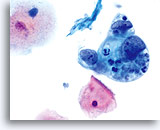

Cytologically, Type I neoplasms show atypical/malignant endometrial cells upon an increased maturation index background. By contrast, Type II neoplasms usually show upon an atrophic background. On ThinPrep samples the endometrial cells will be well preserved and may appear in 3-dimensional crowded groupings of varying sizes as well as small flat sheets containing few cells. The cells usually appear larger than their normal counterpart and the groups have smooth, sometimes scalloped borders giving them a papillary configuration. The cytoplasm is finely to discretely vacuolated and some larger vacuoles can be observed compressing the nucleus to one side of the cell as well as occasionally exhibiting polymorphonuclear cell engulfment. Nuclear features vary dependent upon the grade of the tumor. In general, as the tumor becomes less differentiated, the nucleus tends to round up with an associated gradual increase in nuclear area (µm2), size and number of nucleoli, irregularities in the distribution and coarseness of the chromatin and thickening of the nuclear membranes.

Polymorphonuclear cells may be engulfed in the cytoplasm. 60x

Overall cell size is usually larger than the normal counterpart. 60x

Nuclei “round up” compared to the normal nucleus. 60x

Nuclear membranes may be thickened. 60x

Chromatin may be clumped and irregularly distributed. 60x

Nucleoli are common and vary in frequency, size and number. 60x

Tumor diathesis and single malignant cells may be noted. 60x

Tumor diathesis may be present and appears as a “woven shroud” with a denseness or linear presentation of debris in the center and a frayed or pulled out appearance of the material around the edges of the group. 60x

Endometrial adenocarcinoma 60x